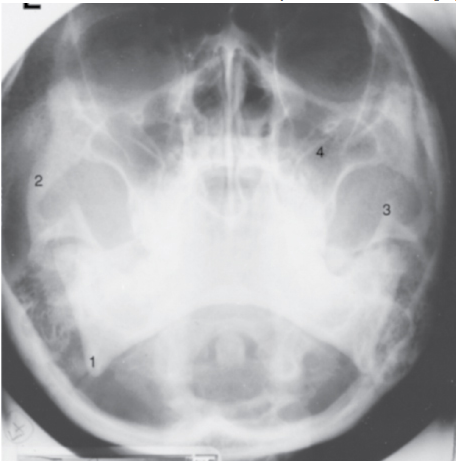

What is the anatomic structure indicated by number 3 in the radiograph in Figure 6–20?

B - Coronoid process

A parietoacanthial projection (Waters position) of the skull is shown. The chin is elevated sufficiently to project the petrous ridges below the maxillary sinuses. The zygomatic arch is well demonstrated, as are the mandible, its angle, and the coronoid process. The coronoid process corresponds to the structure labeled number 3.

What is the anatomic structure indicated by number 1 in the radiograph shown in Figure 6–20?

A - Mandibular angle

A parietoacanthial projection (Waters position) of the skull is shown. The chin is elevated sufficiently to project the petrous ridges below the maxillary sinuses (number 4). Note that the foramen rotundum is seen near the upper margin of the maxillary sinuses. Other paranasal sinus groups are not well visualized in this position, although a modification with the mouth open may be taken to demonstrate the sphenoidal sinuses. This is also the single best projection to demonstrate the facial bones. The zygomatic arch (number 2) is well demonstrated; the mandible, its angle (number 1), and the coronoid process (number 3) are also well demonstrated. The odontoid process is seen projected through the foramen magnum. The mastoid air cells are seen adjacent to the mandibular angle as multiple small, air-filled, bony spaces.

Which of the following structures is illustrated by the number 2 in Figure 2–21? A - Maxillary sinus B - Coronoid process C - Zygomatic arch D - Coracoid process

C - Zygomatic arch The parietoacanthial projection (Waters method) demonstrates a distorted view of the frontal and ethmoidal sinuses. The maxillary sinuses (number 4) are well demonstrated, projected free of the petrous pyramids. This is also the best single position for the demonstration of facial bones. The mandibular angle is illustrated by number 1, the zygomatic arch by number 2, and the coronoid process by number 3.